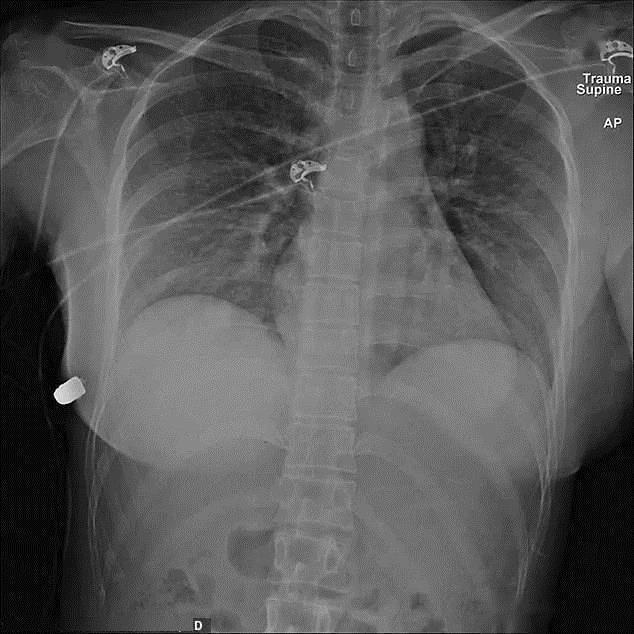

加拿大一名女子遭遇枪击时,弹头原本射入左前胸,其弹道轨迹正好伤及心肺,但她胸前的硅胶假体使弹头向右倾斜,在完全停止射击之前,再次射入右胸。最后,这颗子弹只造成了穿透性枪伤和一根肋骨骨折,而内脏却没有任何损伤,算是不幸中的万幸。

这个女人的主治医生后来向采访人员透露,她是有文献记录以来第一个被隆胸假体拯救的幸运儿,直到2020年,这份罕见的意外研究报告才在国际著名的医学学术期刊《SAGE医学》上发表,全球也只有几个地区出现类似事件。利用 X射线影像观察,医生发现假体奇迹般地使弹头以接近直角的速度高速穿越体内,而不伤及器官。伤员在手术后只移除了植入物,清洗伤口,使用了短期的抗生素就痊愈了。

【 幸存|隆胸硅胶假体还能防弹一女子枪口下幸存,医生看完一脸懵】通过X光观察,弹头几乎没有任何变形,证明硅胶没有受到很大冲击,被子弹穿过后仍能保持原来形状,再加刁钻的射击角度,提供了可以使子弹偏斜的空间,不打死人也可以说得通。距离远,动能小,或许更能解释“假胸防弹”的原因,只不过碰巧有人不幸中枪罢了。(文/山峰)